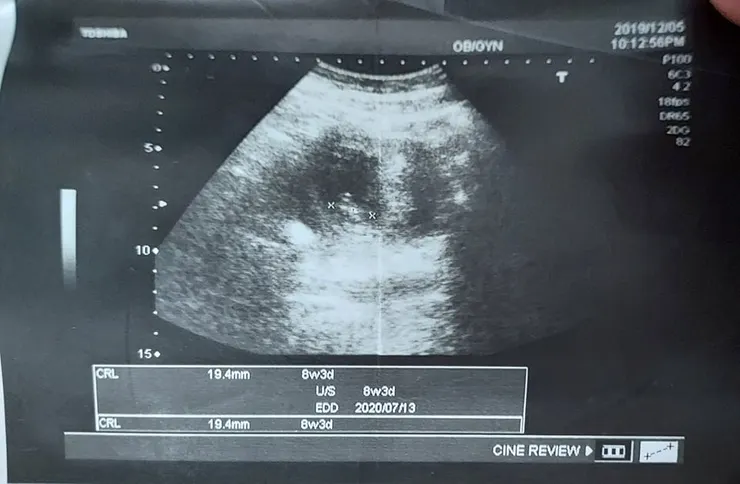

2020.12.5(六)PM10:12

醫生當然是非常恭喜我們確定懷孕了,我也滿高興但也滿還怕的,高興的是不用吃甚麼偏方調身體,太恐怖了,因為婆婆在菜市場有賣饅頭阿姨和他說。害怕的是每次想到生小孩,我就覺得我會死掉,喔!對了,下次產檢才會拿媽媽手冊,醫生也沒說甚麼,就是說好吃好睡,多休息。